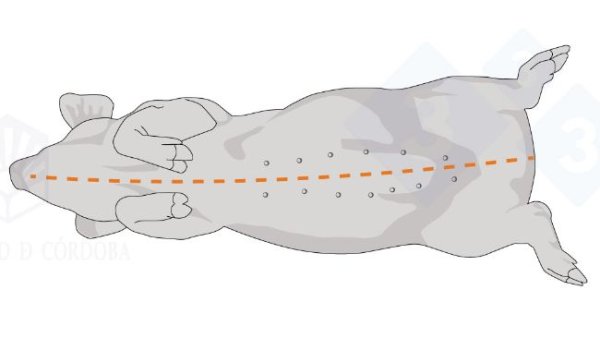

In den ersten beiden Kapiteln haben wir uns mit der Nekropsie in seitlicher Dekubitus-Lage befasst. In diesem dritten Kapitel behandeln wir die Nekropsie in Rückenlage.